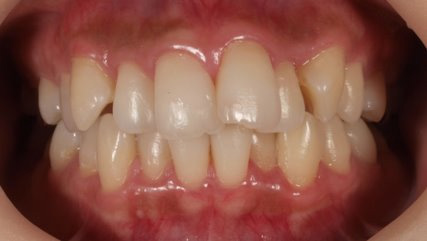

治療前

治療終了前